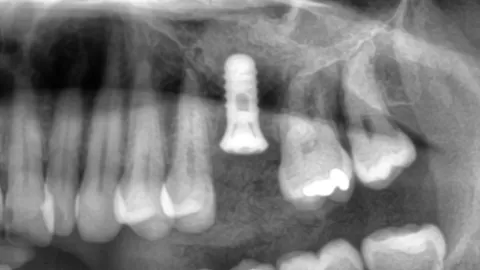

Sinuslyft och Tandimplantat – Så Återställde Vi Benvolymen för en Stabil Implantatbehandling

Läs hur vi med hjälp av sinuslyft och benmaterial kunde möjliggöra stabil implantatbehandling i överkäken trots benbrist.